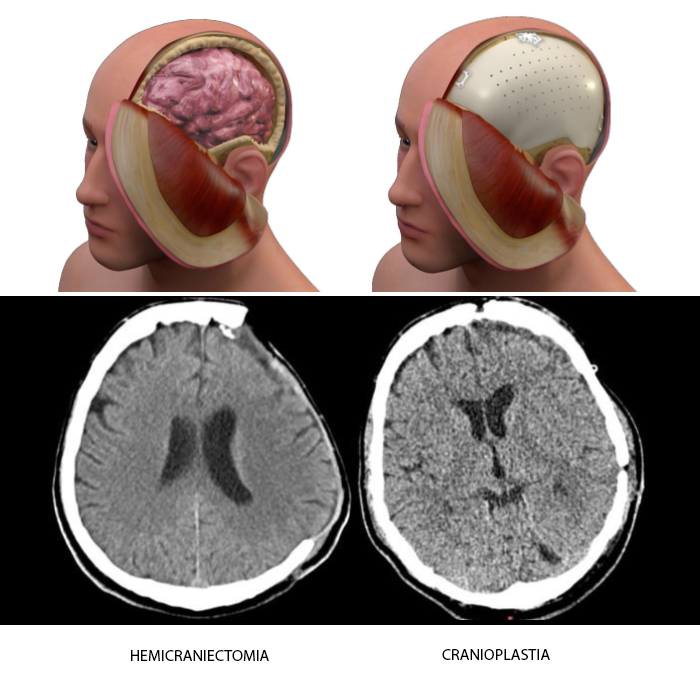

A cranioplastia é um procedimento cirúrgico especializado destinado a reparar defeitos ósseos no crânio. Esses defeitos podem resultar de operações anteriores, traumas, infecções ou tumores. O principal objetivo da cranioplastia é restaurar o contorno natural do crânio, utilizando o osso original do paciente ou enxertos personalizados feitos de materiais como titânio, substitutos ósseos sintéticos ou biomateriais sólidos.

A cranioplastia é essencial não apenas do ponto de vista estético, mas também para garantir que o cérebro esteja adequadamente protegido contra traumas diretos. A ausência de uma parte do osso craniano pode levar a alterações significativas na dinâmica cerebral, incluindo:

- Síndrome do Trefinado: complicação neurotraumatológica que causa deterioração neurológica após a remoção de uma parte significativa do osso craniano (hemicraniectomia), dificultando a recuperação clínica do paciente.

Recentemente, avanços no design assistido por computador e na impressão 3D têm revolucionado a cranioplastia. Agora, é possível criar implantes específicos para cada paciente a partir de uma variedade de materiais como polímeros, cerâmicas ou metais. Um molde do crânio do paciente é utilizado para projetar um implante que se integra perfeitamente, proporcionando uma distribuição ideal da força mecânica em caso de trauma.